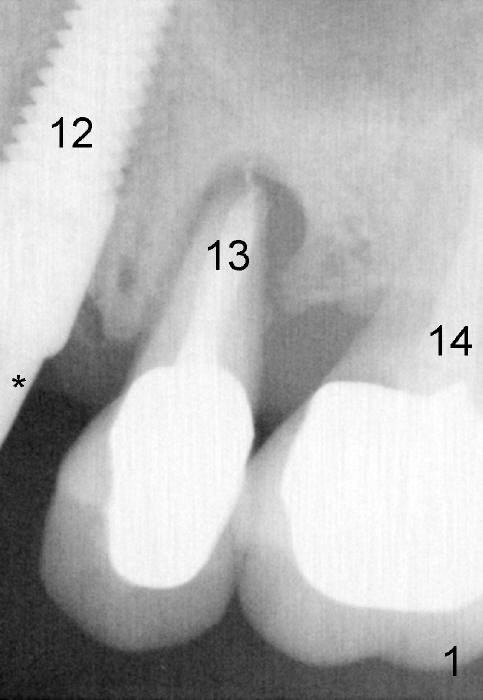

As soon as the tooth #12 is extracted and replaced with immediate implant, the patient feels that pain shifts to the tooth #13 (Fig.1 taken 3 months post implantation of #12; *: abutment). By the 7th months postop (Fig.2 C: crown), the patient agrees to have a 2nd implant for the tooth #13. Thorough debridement of the socket is planned. Sinus lift is expected. Take preop PA and photos.